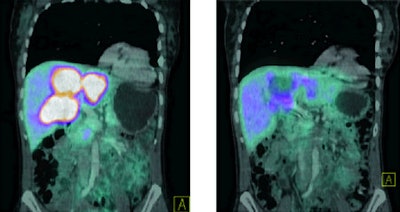

In this study, Bi-213 DOTATOC was synthesized using a microwave-assisted labeling protocol. A total of 21 patients who previously had shown resistance to treatment with the radioactive isotope yttrium-90 or lutetium-177 DOTATOC were treated with escalating doses of Bi-213 DOTATOC therapy. Doses ranged from 1 to 10 GBq up to 21 GBq.

The researchers then assessed response with gallium-68 DOTATOC PET/CT, contrast-enhanced sonography, MRI, digital subtraction angiography, and tumor markers. In addition, markers were monitored for hematologic, kidney, and endocrine toxicity during and after treatment.

| Response to Bi-123 DOTANOC treatment observed in patients with tumors resistant to previous therapy with yttrium-90 and lutetium-177. Image above shows shrinkage of liver lesions and bone metastases after therapy with 11 GBq of Bi-123 DOTANOC. Image below shows response of multiple liver lesions after therapy with 14 GBq of Bi-123 DOTANOC. Images courtesy of SNM. |

Morgenstern and colleagues found that the labeling protocol for Bi-213 DOTATOC provided reliable doses of the treatment at a clinical level. In addition, patients tolerated the increasing doses well, and there was no acute kidney, endocrine, or hematologic toxicity.

Most importantly, the researchers observed shrinkage of the primary tumors, as well as liver and bone metastases.